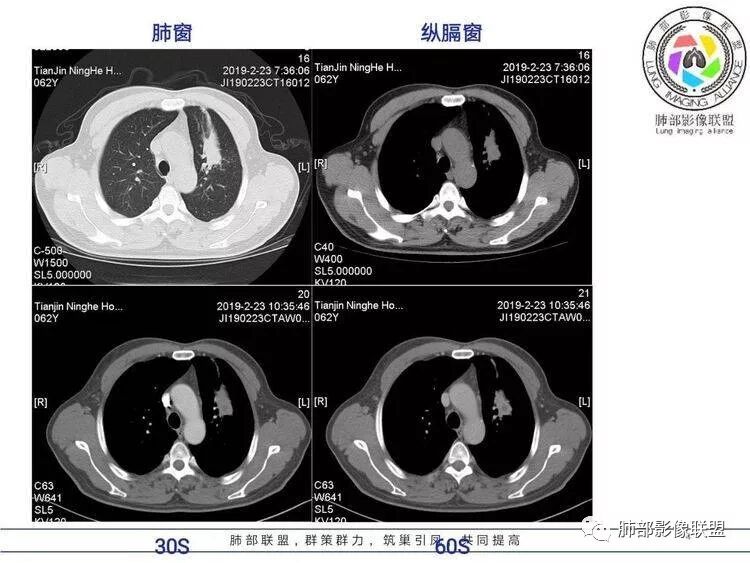

病例资料

王秀仙:左肺上叶肿块,边缘平直收缩,周围可见长索条,轻度强化,密度不均可见低密度坏死,考虑结核。鉴别腺癌。Yiren  Sishui(厶水伊人):晨读:左肺上叶肿块,近胸膜侧光滑,提示符合淋巴回流病变,周围条索,符合肉芽肿性病变,环形强化,中心坏死,考虑结核可能luys:左肺上叶病变,沿支气管分布,边缘平直收缩,周围见长索条,轻度强化,伴边界可见低密度坏死灶。考虑特殊感染。灶内支气管中断,临床以咯血就诊,鉴别肿瘤。博麟:左上胸廓稍缩小,长条索病灶,冠状位似见支气管截断,坏死边界似乎欠清,猜个纤维条索基础上合并瘢痕癌红日东升:晨读:左上叶结块,前缘有粗大索条向前延伸,邻近前联合线明显左移,提示收缩明显。结块边缘平直、收缩;增强结块及索条明显强化,内血管走行自然,坏死灶周围似见三层结构;考虑炎性病变。wonderful:肿块实性边缘光滑  考虑良性病变 合并咯血 。结核或曲霉玫:左肺上叶不规则形软组织密度肿块影,边界清晰,期内密度不均匀,可见坏死,病灶向前呈条索状延伸,矢状位病灶形态欠规整,似有血管中断,考虑恶性病变可能,待除外结核?张帅:左肺上叶病变,病变周围平直,长毛刺,病灶内可见低密度区及支气管征,矢状位提示前段阻塞,病灶内气管不规则扩张,病灶周围有卫星灶,考虑良性病变:结核?我心飞翔:病灶边缘平直,中央可见坏死,周围磨玻璃边界欠清,考虑炎性病变张延军:左肺上叶尖后段肿块,边缘以平直为主,局部膨隆,内见片状坏死区,边界欠清,相应尖后段支气管闭塞,考虑占位并不张,腺癌?建议抗炎治疗后复查丽:左肺上叶病变,边缘平直,并可见长索条,增强后密度不均,可见坏死,首先考虑结核,但重建后支气管走形欠连续,似有截断,恶性待排毛勤香:左肺上叶病灶,边缘平直为主,周围索片影,增强强化不均匀,内有坏死,重建支气管走行欠规则,似有截断,老年男性,需排除恶性(鳞癌?)并阻塞性肺炎可能王萍:左肺上叶团片,大部分边缘平直、凹陷,周围见少许条片模糊影,增强内见坏死区,余区域较均质,其内支气管部分通畅,部分变窄。咯血病史,无发热,考虑肉芽肿性炎可能性大,结核或放线菌等,肿瘤待排THINKER:左上叶,占位,围绕尖后段支气管,U型凹丶平直,长索条,有轻强化及低密度,考虑良性的,首选OP,老年不发热丶咯血,鉴鳞癌、TB飞鹰行动:左肺病灶,有明显的收缩表现,增强后病灶内部可见低密度无强化区,病灶内支气管轻度扩张呈串珠状改变,支持炎性病变,结核可能性大。杨泽锋:支持炎性病变伴小脓腔形成,但不支持结核,因为病灶内可以可见血管影THINKER:问一下各位老师:这个给的强化,是肺动末期丶主动脉未期`延迟期?大雄:老年男性,左肺上叶前段条片状实变影伴周围长条索,境界清晰,边缘部分锐利光滑、部分毛糙,增强可见中央局部坏死,周围无强化区轻中度均匀强化,无钙化,无明显卫星灶,无胸膜明显牵拉凹陷。病灶整体收缩力有,张力不明显,肿瘤概率小。临床无明显急性感染症状,倾向于慢性增生性炎症,累及段支气管,引起了咯血。结核多见,但慢性结核肉芽肿一般强化没这么明显。OP不除外。老年男性如果有长期吸烟史,鳞癌不能完全排除,鳞癌的坏死强化都符合,鳞癌收缩力也不强,形态更是变化无常左手:老年男性,咯血,左肺上叶长条样结节,边缘见牵拉影,支气管堵塞,病灶内见坏死,坏死边缘偏清,考虑鳞癌,鉴别结核宇宙星空:支持恶性。鳞癌可能性大。支气管截断及空泡征

Shelia:考虑机化性肺炎伴小脓肿形成?炎性肌纤维母细胞瘤?鉴别癌食客:左肺上叶病灶,边缘平直,周围条片影,增强内见坏死区,内支气管部分通畅,咯血病史,无发热,考虑结核,肿瘤不除外。管洪林:左肺上叶尖后段病变,整体边缘平直,部分稍收缩,临近长索条影,胸膜缘可见轻度牵拉,增强后整体强化明显,其内可见低密度类圆形坏死区,边界清,首先考虑op并小脓肿形成,但部分层面显示小支气管受阻,是否层面原因?管洪林:若是支气管阻塞,鳞癌作为鉴别雪上一枝蒿(陈显静):他这个动脉期是不是不是很明显啊,觉得跟静脉期差不多,强化值也不好分辨?徐超:左肺上叶实变,边缘平直,周围无磨玻璃及卫星灶,病灶内坏死,强化后边界清楚,无壁结节,余病灶轻中度均匀强化(对比肌肉),增强后血管显影清楚自然,未见破坏边缘毛糙,血管旁条形无强化区(粘液?)整体符合炎性特点,炎性假瘤或op可能,伴小脓肿;结核放后面待排(结核病灶内血管完好,边缘清楚,且强化近中度,不是很合理,肉芽肿到也可以)。红日东升:平扫和强化窗宽窗位不一样良孑:左上实变,有平直及长毛刺,其内支气管牵拉性扩张,提示收缩力较强,无卫星灶,强化不支持TB,均匀强化,无分叶不支持鳞癌,影像上提示慢性进程,考虑OP并脓肿,鉴别炎肌母。

南边:应该是前段吧。前段的支气管怎么样?

南边:坏死如何?

南边:还是支持炎性吧